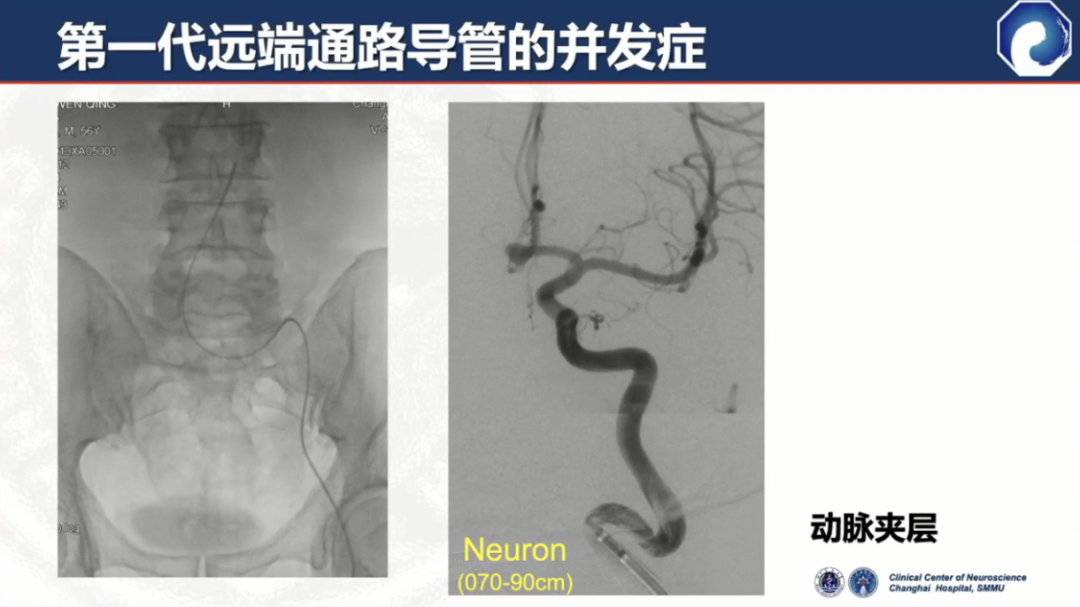

与普通导引导管相比,头端柔顺性增加,但并发症发生率仍比较高,如:夹层、血管破裂、载瘤血管闭塞等